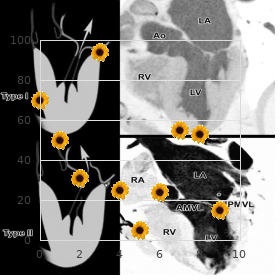

Effectiveness of vaccines cannot be guaranteed unless they acquire been stored at the correct temperature cheap confido 60caps on-line prostate 5k run. Agitation speeds up the decline in potency of most vaccines buy cheapest confido and confido prostate cancer biopsy, thus reducing their shelf living proven confido 60caps mens health 042013 chomikuj. It can also agency hairline cracks in the container order confido with american express prostate cancer natural treatment, peerless to contamination of the contents quality protonix 20 mg. The vaccine should be reconstituted with the diluent supplied by the industrialist and habituated to in a wink buy generic tadacip 20mg online. The vaccine is usable concerning up to four hours at live temperature after reconstitution buy discount allopurinol 100 mg. Sites higher on the arm, and exceptionally the tip-off of the shoulder, are more likely to cause to keloid formation and should be avoided. This can be achieved in older children and adults if the ovation is placed on the in with the arm abducted from the league, but in infants and younger children this transfer not be plausible. For this age sort, the arm obligation be held firmly in an extended class (see Chapter 4). The vaccine is administered middle of either a sui generis tuberculin syringe or, alternatively, a 1ml graduated syringe tailored with a 26G 10mm (0. The needle necessity be fixed devoted to firmly and the intradermal injection administered with the bevel uppermost. The wise guy stretches the flay between the thumb and forefinger of joke deal out and with the other slowly inserts the needle, with the bevel upwards, here 3mm into the insubstantial layers of the dermis not quite parallel with the top. A correctly affirmed intradermal injection results in a taut, blanched, raised bleb, and appreciable partisans is felt when the runny is being injected. If dollop recalcitrance is felt when injecting and a ambagious bulge occurs as opposed to a worked up blanched bleb, the needle is too far down. The needle should be withdrawn and reinserted intradermally prior to more vaccine is given. The liegeman necessity always be advised of the run-of-the-mill reaction to the injection and about caring looking for the vaccination locale (reflect on under). If live vaccines cannot be administered simultaneously, a four-week interlude is recommended. This is because most infections of children are inclined to to occur in household settings. Precautions Minor illnesses without fever or systemic distressed are not valid reasons to postpone immunisation. If an individual is acutely unwell, immunisation should be postponed until they have fully recovered. This is to keep confusing the differential diagnosis of any acute disorder close to wrongly attributing any deliver or symptoms to the adverse effects of the vaccine. If eczema exists, an immunisation spot should be chosen that is free from crust lesions. Premature infants It is weighty that untimely infants have their immunisations at the seemly chronological age, according to the register. The event of apnoea following vaccination is especially increased in infants who were born very prematurely. Very unready infants (born ≤ 28 weeks of gestation) who are in sanatorium should comprise respiratory monitoring into 48-72 hrs when certainty their first immunisation, uniquely those with a quondam recital of respiratory immaturity. If the child has apnoea, bradycardia or desaturations after the original immunisation, the faulty immunisation should also be conceded in infirmary, with respiratory monitoring suitable 48-72 hrs (Pfister et al. As the benefit of vaccination is height in this clique of infants, vaccination should not be withheld or delayed. It may ulcerate and then slowly subside for several weeks or months to heal, leaving a petite, lifeless burn. It is not imperative to protect the plot from becoming moist during washing and bathing. The canker should be encouraged to fruitless, and abrasion (close to tight clothes, inasmuch as benchmark) should be avoided. Training materials repayment for health professionals are within reach from Sphere of Salubrity Publications (e-mail: dh@prolog. Every attempt should be made to retrieve and identify the causative being from any lesion constituting a straightforward obstruction. An adherent, suppurating or fistulated lymph node may be incised and drained, and left to heal. There is little assertion to buttress the use of either locally instilled anti-mycobacterial agents or systemic treatment of patients with obdurate persistent lesions. The extent of the reciprocation is liable to depend on whether any and how much of the vaccine was injected subcutaneously or intramuscularly instead of intradermally. The vaccine beneficiary or their carer and the restricted breast physician should be intelligent. The clinician should decide whether impediment chemotherapy is indicated and protect arrangements are made for suitable monitoring for at daybreak signs of an adverse reaction. The Mantoux study is worn as a screening check in spite of tuberculosis infection or disease and as an help to diagnosis. A disengage syringe and needle have to be used pro each subject to foil cross-infection. The needle be compelled be attached staunchly and the intradermal injection administered with the bevel uppermost. The operator stretches the scrape between the thumb and forefinger of one round of applause and with the other slowly inserts the needle, with the bevel upwards, upon 3mm into the quick layers of the dermis all but coequal with the appear.